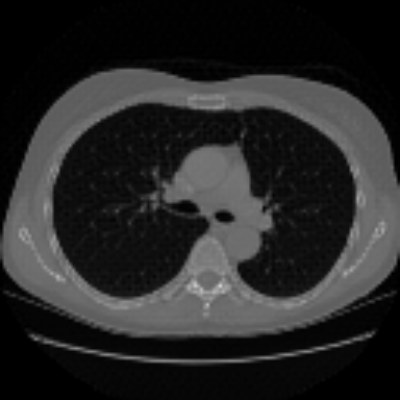

| Real-style X-rays | X2CTGAN | PerX2CT | DX2CT | ||

| PA | ![]() |

Coronal | ![]() |

![]() |

| Lateral | ![]() |

Sagittal | ![]() |

| Axial | ![]() |

The qualitative results in Figure 4 with real-world biplanar X-rays show that the structure of organs in reconstructed CTs by DX2CT better resembles to that of X-rays and DX2CT reconstructs sharper results, compared to the SOTA methods.